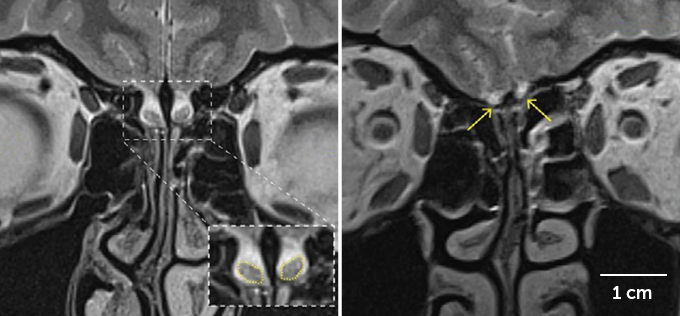

MRI scans of the women’s brains revealed that where most people have two olfactory bulbs, these two appeared to have cerebrospinal fluid instead. To the researchers, this indicated that the women didn’t have olfactory bulbs.

A typical olfactory bulb has about 5,500 nerve clusters called glomeruli. With the MRI resolution used, the researchers calculate that they should be able to see olfactory bulbs with at least 10 glomeruli — about 0.18 percent the size of a normal bulb. But it’s possible the women could have even smaller olfactory bulbs, Sobel acknowledges.